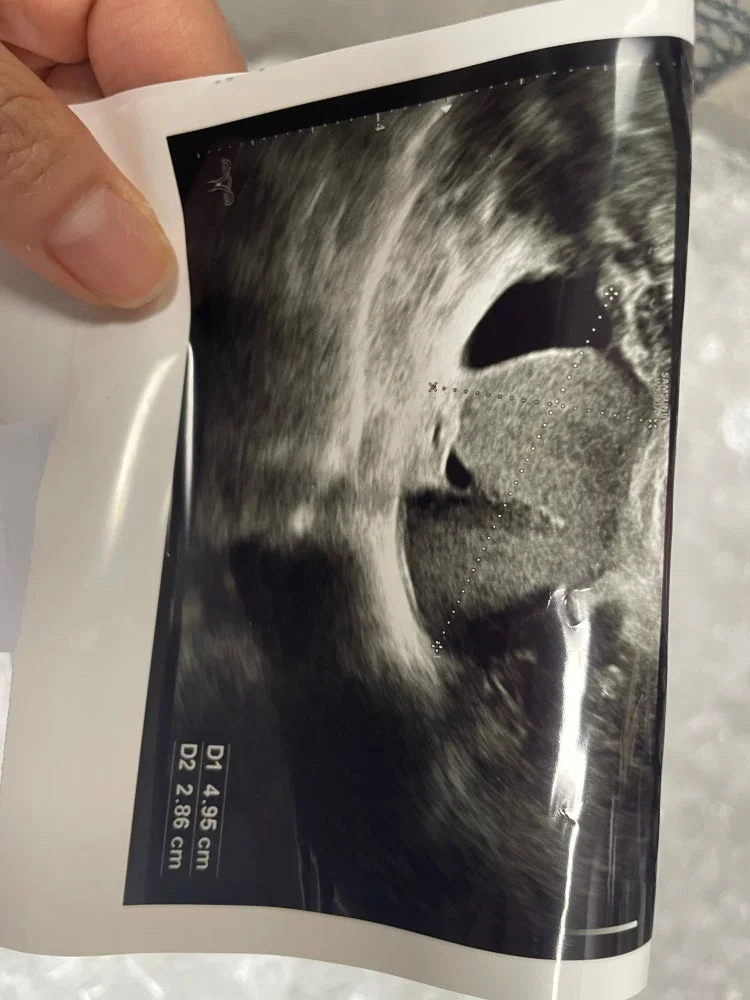

초음파 사진 한번만 봐주세요ㅠ

모양이 좋지않다고 두군대 갓는대

한곳은 물혹이 모양이 좋지않다고 난소암 피검사햇고

한곳은 난소암은 아니고 자궁내막증 확정받앗어요

* 초음파 사진: 올려주신 초음파 사진만으로는 정확한 진단을 내리기가 어렵습니다. 물혹의 크기, 모양, 내부 구조, 주변 조직과의 관계 등을 종합적으로 판단해야 합니다.